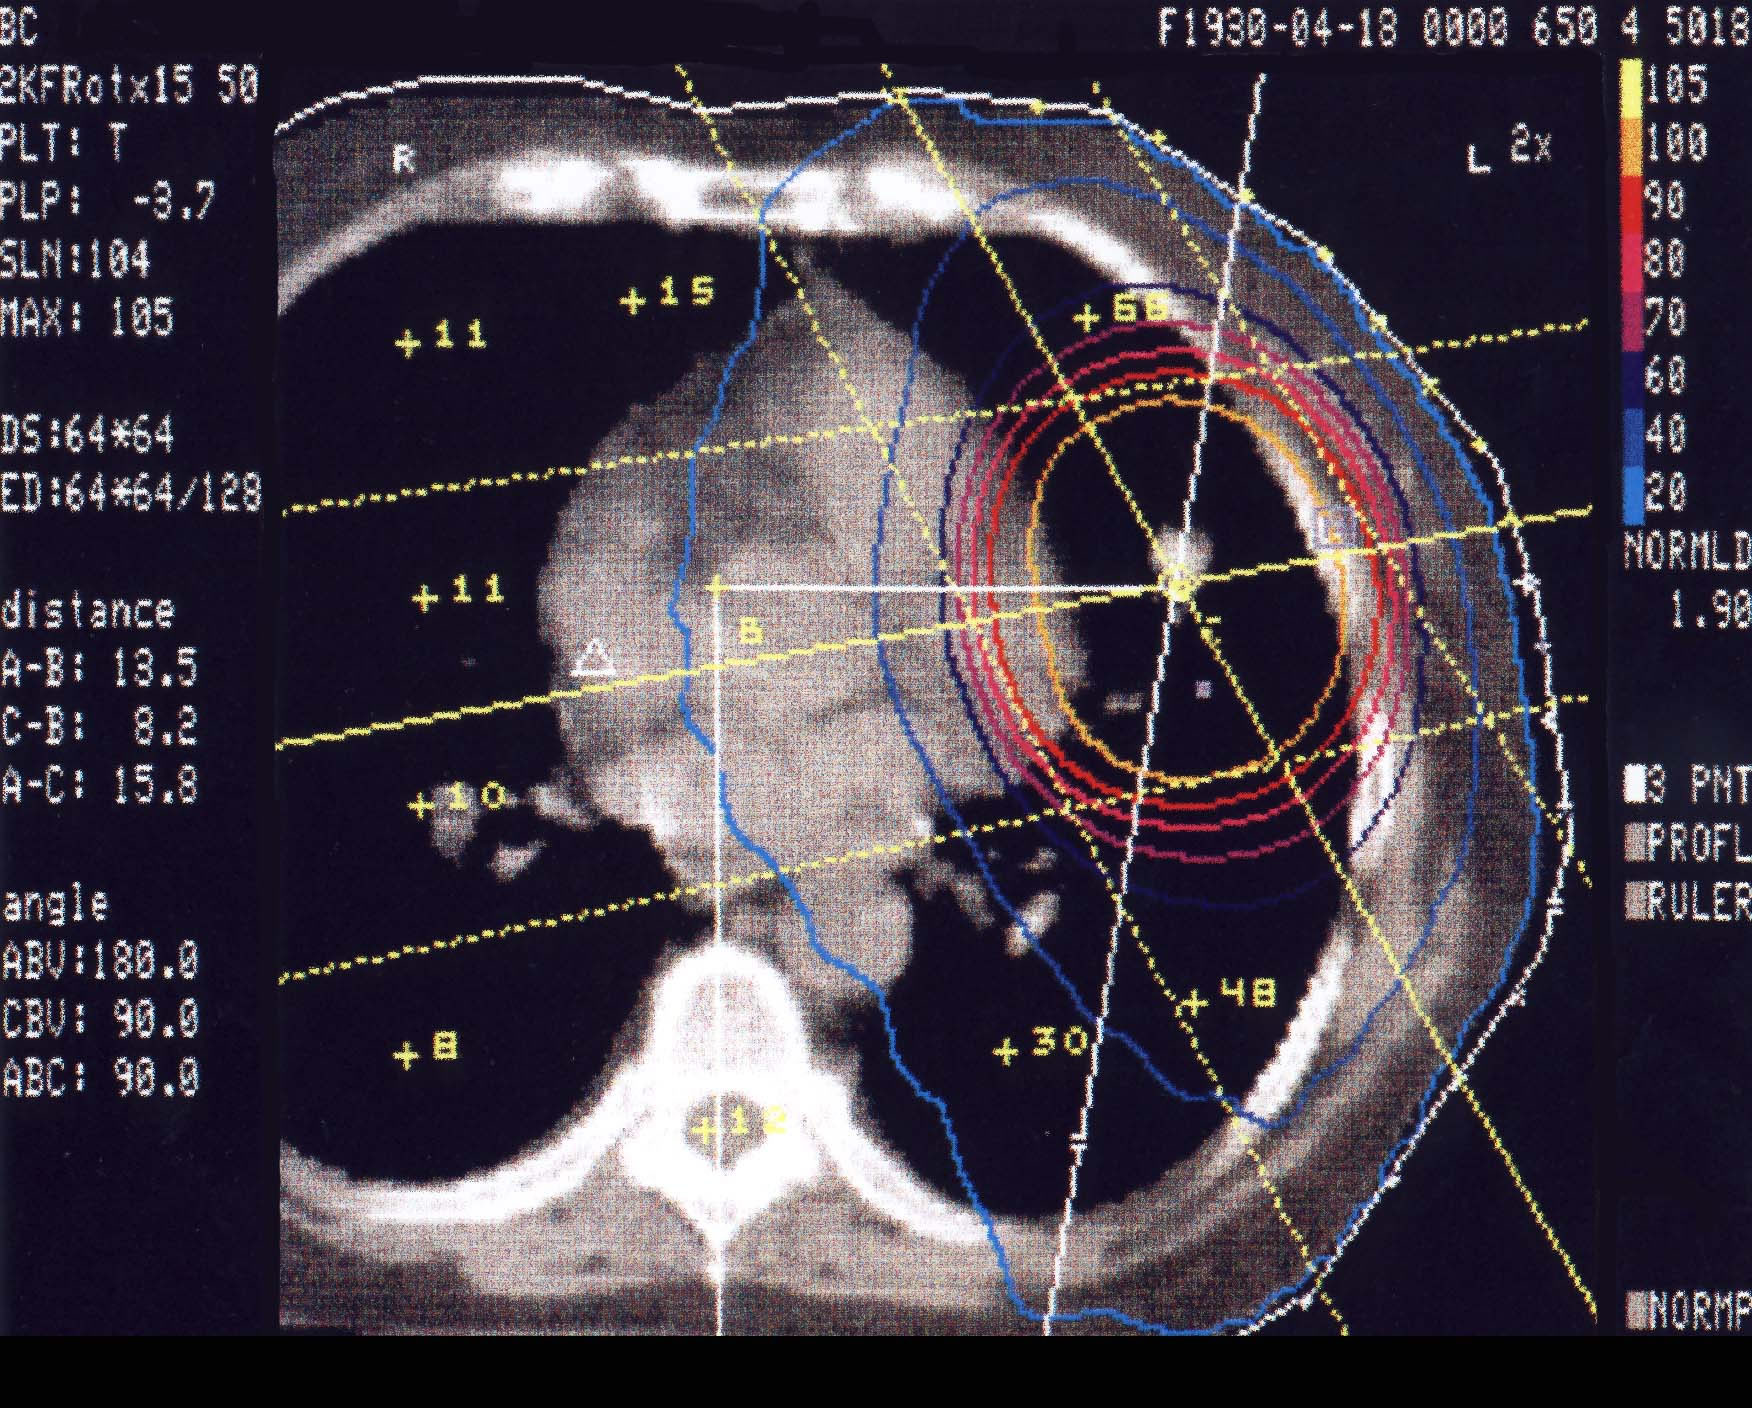

Bronchialkarzinom: Bestrahlungsplan